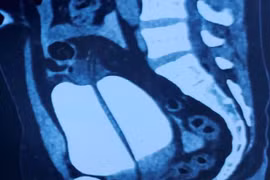

Sau một cú ngã tưởng chừng không quá nghiêm trọng, nam thanh niên 29 tuổi ở Sơn La phải nhập viện cấp cứu trong tình trạng vỡ bàng quang.

Nhịn tiểu khi uống bia, người đàn ông 46 tuổi bị vỡ bàng quang nguy hiểm, được các y bác sĩ Bệnh viện Nhân dân 115 cứu sống.